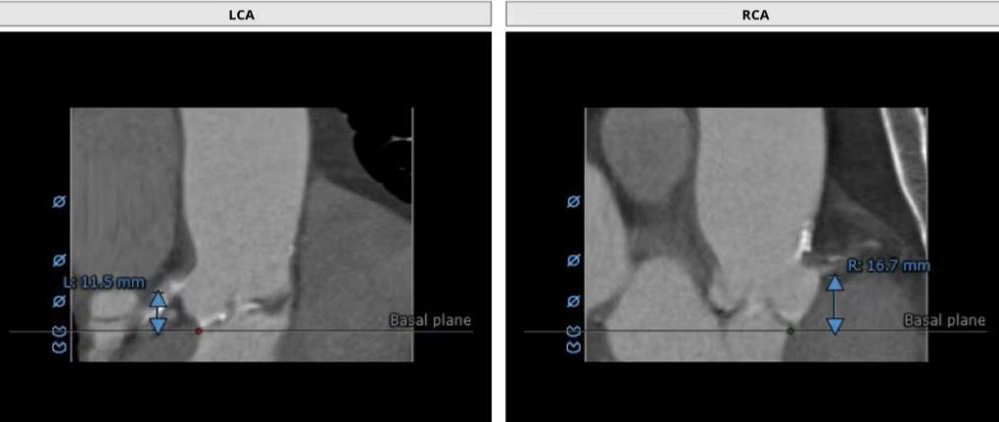

左右冠脉高度:LCA:11.5mm RCA:16.7mm